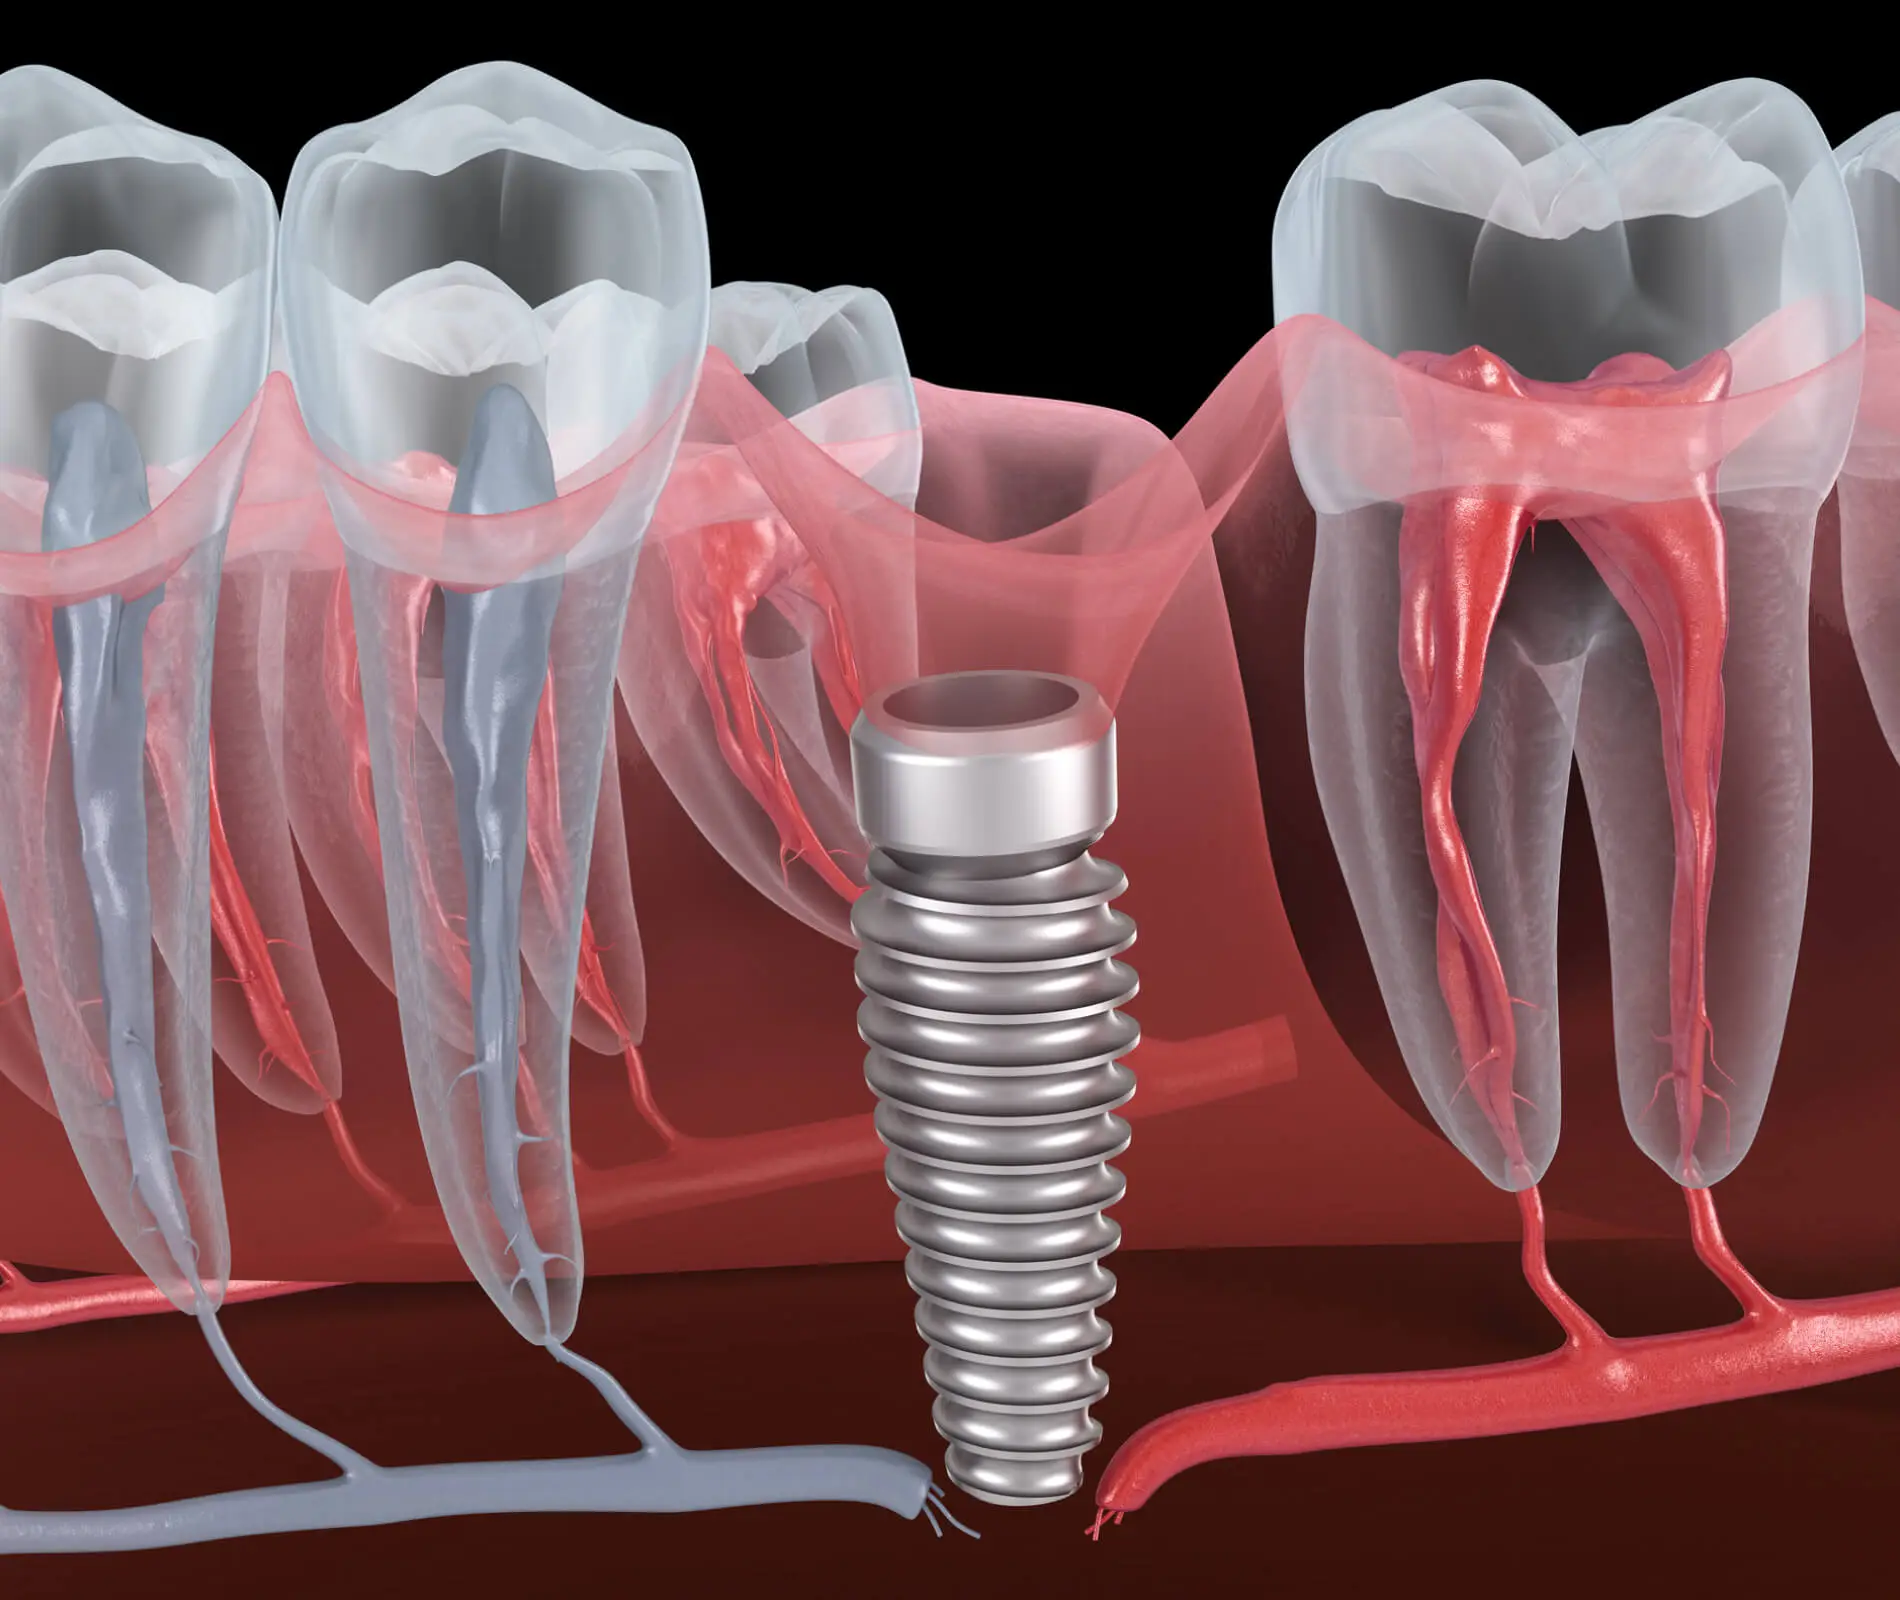

Dental Implant Complication . However, dental team members may be increasingly faced with addressing biological and prosthetic implant complications at the. Frequent mechanical complications include abutment screw loosening, abutment fracture, and prosthesis fracture of both the veneer and the framework. The possible treatment options for implant failure include the replacement of a faulty implant right away with one with a larger. While dental implants are increasingly becoming the choice of replacement for missing teeth, the impediments associated with them are. If you’re scheduled to have dental implant surgery, or if you currently have an implant, here’s what you need to know about implant failure and other potential complications. It’s a procedure where your dentist places a metal. Dental implants are an effective way of replacing lost or damaged adult teeth.